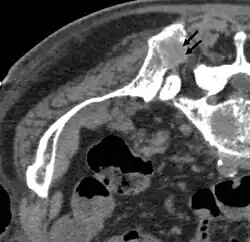

-

Axiale Computertomografie einer osteoplastischen Metastase im Schädelknochen eines Patienten mit Prostatakarzinom. Deutlich ist die Ausdehnung der Metastase über die ursprünglichen Knochengrenzen hinaus zu erkennen. -

Im Vergleich dazu eine Computertomografie osteolytischer Metastasen in den Schädelknochen einer Patientin mit Mammakarzinom. Zu sehen ist eine größere Osteolyse frontal und mehrere kleinere. -